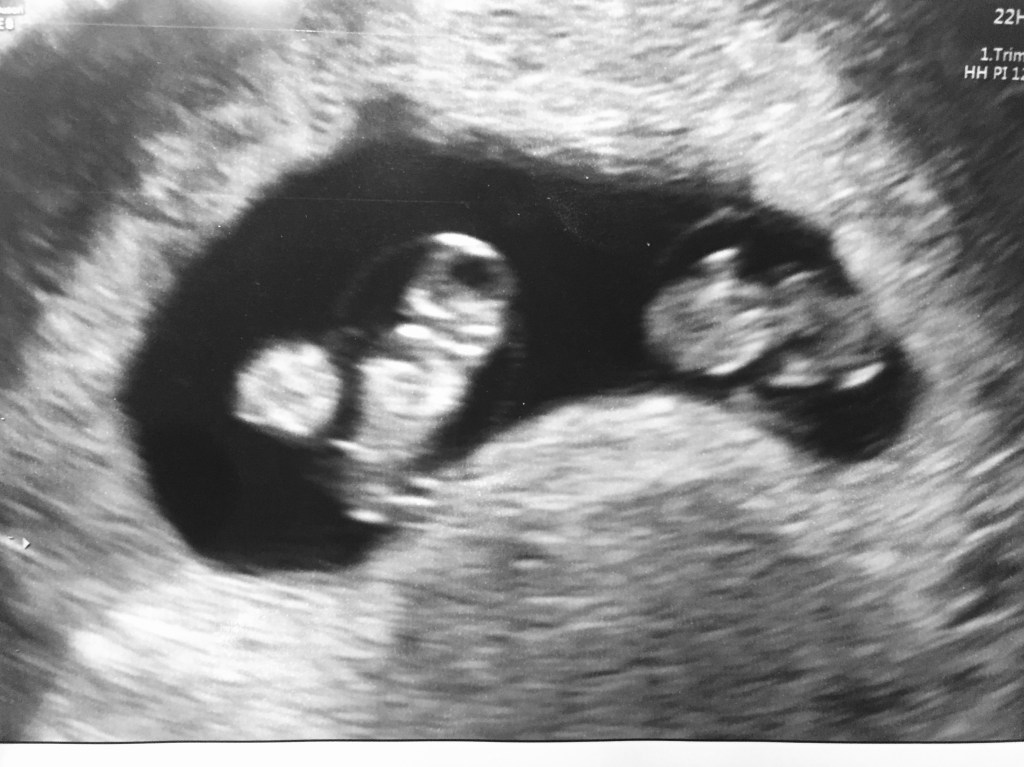

Na het uitblijven van mijn menstruatie een zwangerschapstest gehaald. Was deze nou positief? Op mijn eerstvolgende werkdag in het ziekenhuis even snel met de echo kijken, ja hoor: een vruchtzak te zien. Dolblij dat het in mijn baarmoeder zat en dat er een beginnende zwangerschap groeide was ik in afwachting tot de eerste echo. In de auto naar de verloskundigenpraktijk, waar ik zelf mijn afstudeerstage had gedaan, hadden we het nog even over wat je allemaal op een vitaliteitsecho ziet. Mijn wederhelft wilde geen flater slaan dus grappend vertelde ik dat ze de termijn ongeveer konden schatten met deze echo en hoe de beginnende baby er nu uit zou zien. Hij zei nog: ‘En of het er één is, of misschien wel twee’! ‘Ja, ook dat zou je kunnen zien’, zei ik.

Terug in de auto staarden we naar de echo foto’s die ik in mijn hand had. Vol euforie, ongeloof en in een hilarische stemming want: ‘Oje het waren er echt twee’. Helaas was het voor zowel mijzelf als voor de echoscopist niet duidelijk of we nu een enkel of wellicht geen tussenschot zagen. Lichtelijke paniek, want op mijn werk zie ik helaas nog wel eens de complicaties die ontstaan bij een mono-mono zwangerschap zoals we die in de verloskunde noemen. Dit betekent dat baby’s elkaar in de buik letterlijk kunnen omhelzen zonder tussenschot. Dit brengt extra complicaties met zich mee. Klik hier voor mee informatie over deze zogenoemde zygositeit.

Na de echo ging ik terug naar mijn afdeling. Die avond begon ik mijn dienst op de verloskamers met een glimlach van oor tot oor. In mijn buik zat niet één klein mensje, maar twee, ínclusief tussenschot: opluchting. Helaas wist ik hiermee overigens ook gelijk dat het gevaar nog niet geheel geweken was. Want ook bij een monochoriale (enkel buitenvlies) diamniotische (dubbel binnenvlies) (MCDA) tweeling zijn er net iets meer risico’s dan bij een dichoriale diamniotische (DCDA) tweeling.